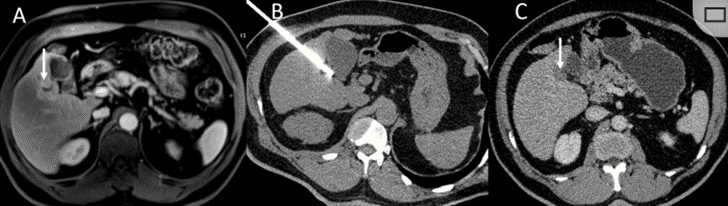

CT引導(dǎo)的冷凍消融

undefined

51歲男性患者,肝移植后復(fù)發(fā)病例

(a) 射頻消融后在病變邊緣顯示殘余增強(qiáng)。

(b) 冷凍消融術(shù)中影像顯示冰球完全覆蓋病變。

(c) 19個(gè)月后隨訪,沒有發(fā)生局部腫瘤進(jìn)展。